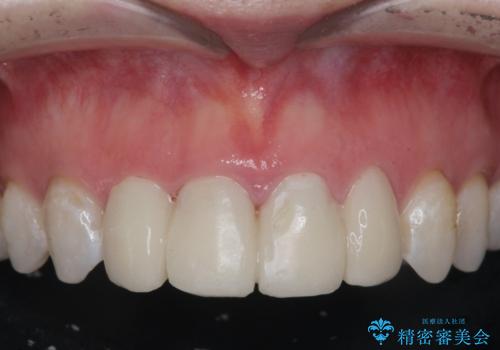

[ セラミック治療 ] 前歯の変色をきれいにしたい

担当医 大元洋佑

![[ セラミック治療 ] 前歯の変色をきれいにしたいの症例 治療前](https://seimitsushinbi.jp/wp/wp-content/uploads/2023/12/8095b301c8ea19cbf7179d372450bebf-500x350.jpg?v=1703129532)

![[ セラミック治療 ] 前歯の変色をきれいにしたいの症例 治療後](https://seimitsushinbi.jp/wp/wp-content/uploads/2023/12/528aed1286d6fd20e773cd5dfb0c7971-500x350.jpg?v=1703129602)